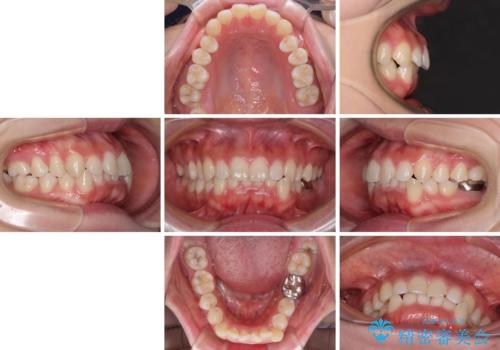

- 前歯のデコボコやクロスバイト、口元の突出感を気にして来院された患者様です。

上下左右の第一小臼歯4本を抜歯して、ワイヤー装置にて矯正治療を行うこととしました。